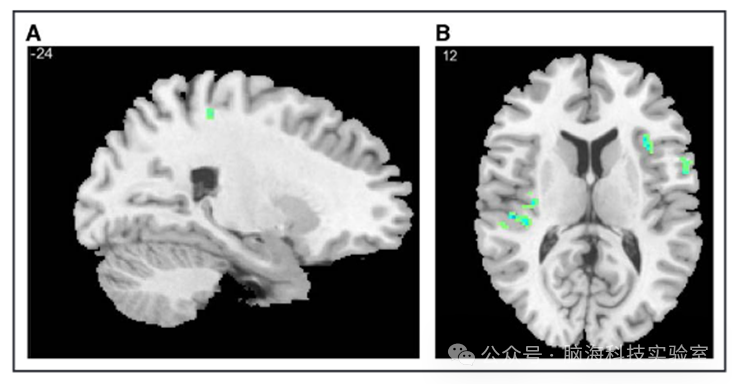

对比P4_INVP3_INV发现,激活区域广泛,与健康P4P5对比类似,包括双侧DLPFC、左侧辅助运动区(SMA)、右侧初级体感皮质、双侧楔前叶、右侧内侧前额叶皮质、右侧角回、左侧颞上回和左侧缘上回(图4)。然而,与中风和健康参与者的充盈期不同,未观察到ACC或岛叶的活动。对比P5_INVP3_INV发现,与P4相比激活区域减少,但左侧DLPFC和右侧下额回的活动持续存在。右侧角回的激活更加显著。此外,与基线相比,双侧前部ACCBOLD信号降低(图4)。

图片

中风幸存者逼尿肌不自主收缩前的脑活动图

中风幸存者在非自主逼尿肌收缩前P4(顶部)和P5(底部)期间血氧水平依赖性(BOLD)效应变化的代表性矢状面和轴向图像。请注意,在P4期间,与几个功能网络相对应的区域广泛激活,在P5期间,激活减弱,显著网络(岛叶、前扣带皮层)中没有BOLD活动。